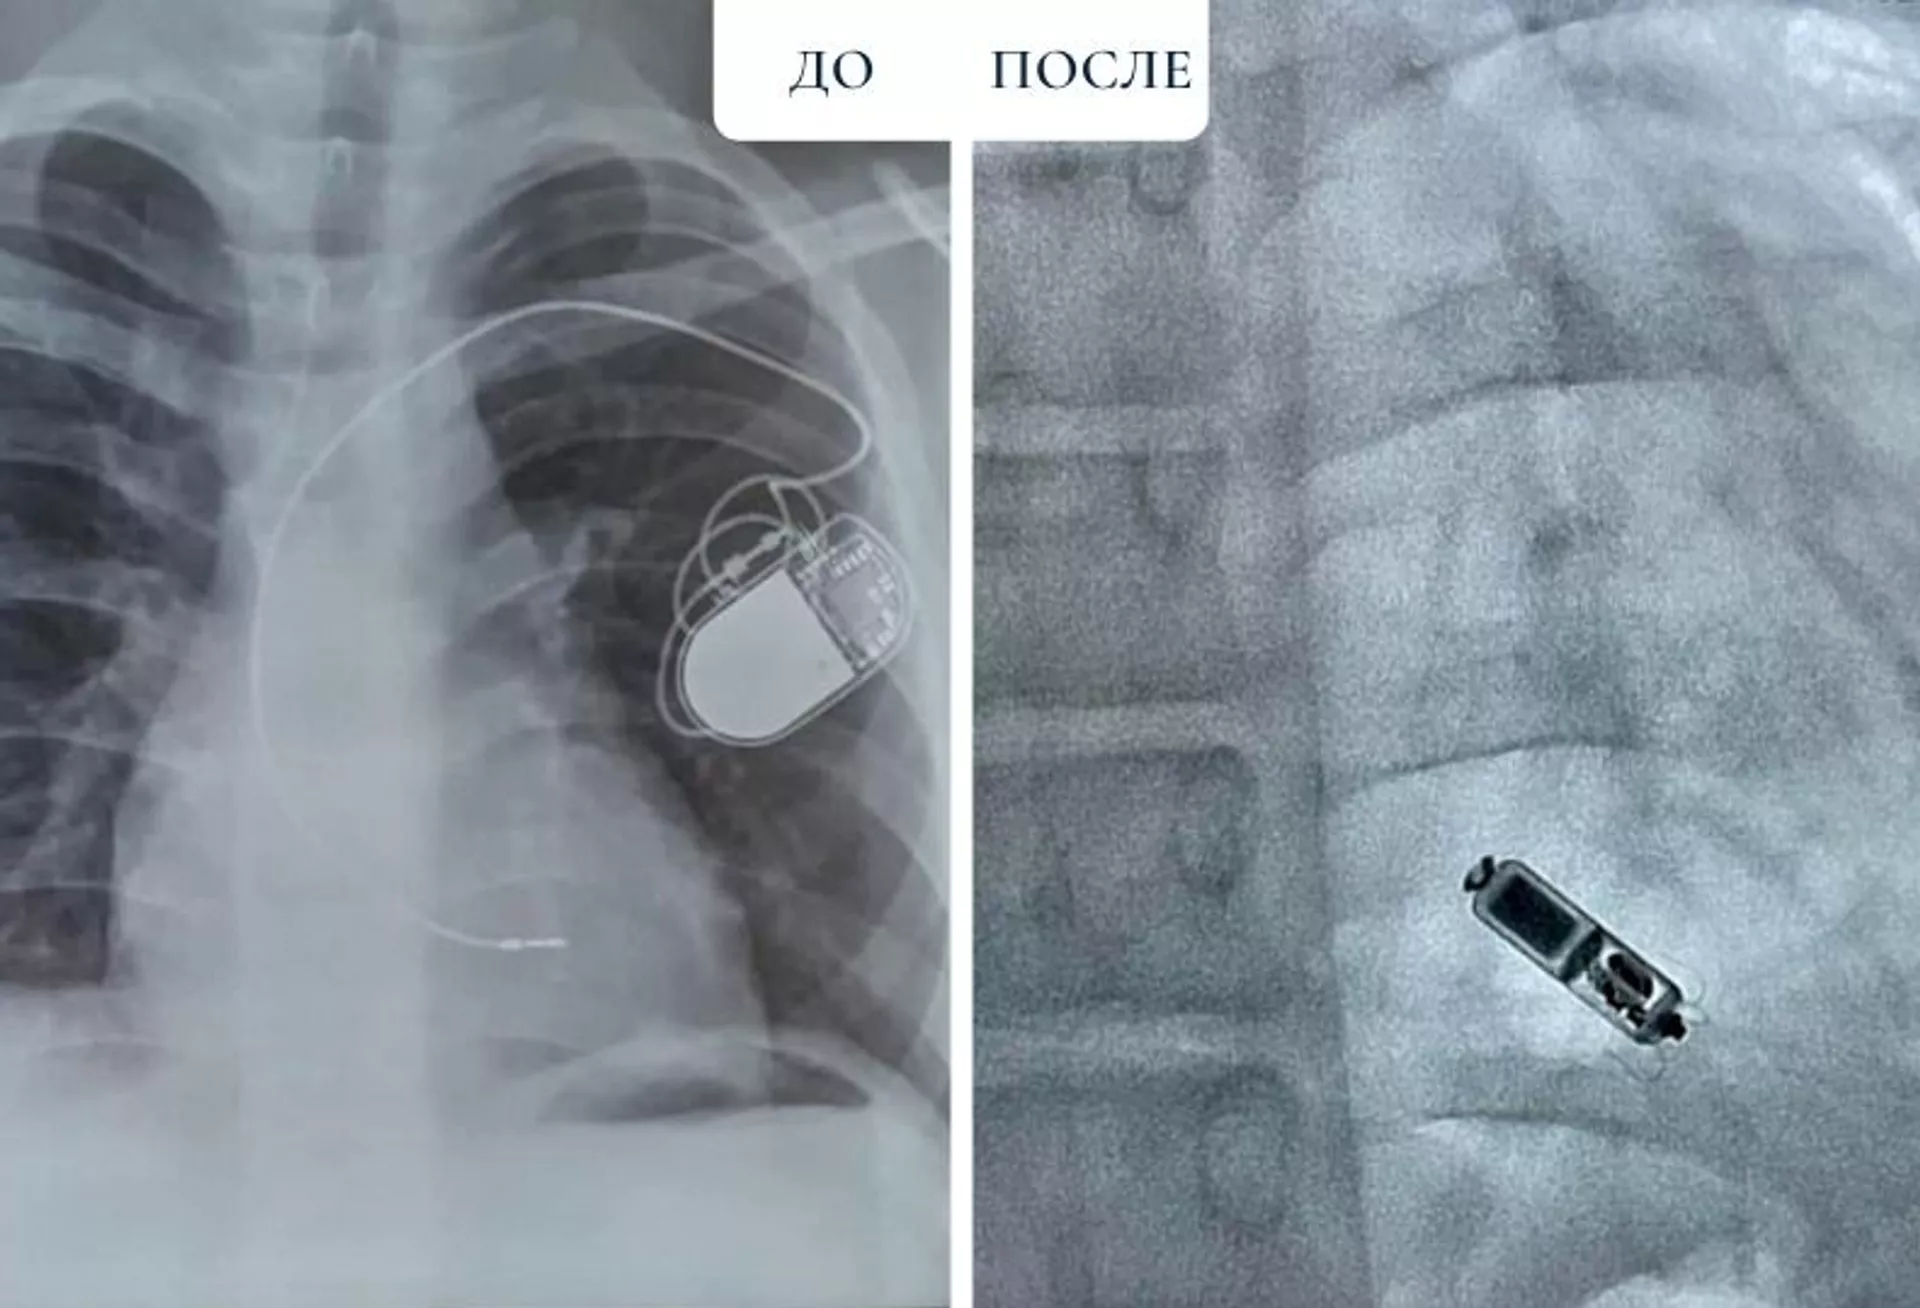

Однако за этот период ребенок вырос, а это означает, что имплантированный ЭКС уже не подходит по размерам: электрод начинает натягиваться. На рентген-снимке это выглядит в виде дуги, в нормальном же состоянии электрод должен быть волнообразным. Существует повышенный риск разрыва электрода, после которого работа сердца снова будет заблокирована.

"Мы решили удалить прежнюю систему ЭКС, так как она уже не подходит пациенту, - рассказывает заведующий отделением интервенционной аритмологии Центра Сердца Аян Абдрахманов. - После чего мы провели имплантацию нового безэлектродного ЭКС Micra AV. Состояние пациента заметно улучшилось, а синхронизация между предсердиями и желудочками достигла 80%".

Micra AV - это самый маленький безэлектродный электростимулятор в мире размером всего с таблетку, имеющий функцию двухкамерной стимуляции. Он устанавливается только в правом желудочке - одной камере сердца. Но работает как двухкамерный за счет распознавания предсердных сокращений. Micra AV помогает синхронизировать работу предсердий и желудочков, при этом исключить осложнения, связанные с электродами. В этом и состоит уникальность данной системы. Проще говоря, этот ЭКС синхронизирует работу сердца.